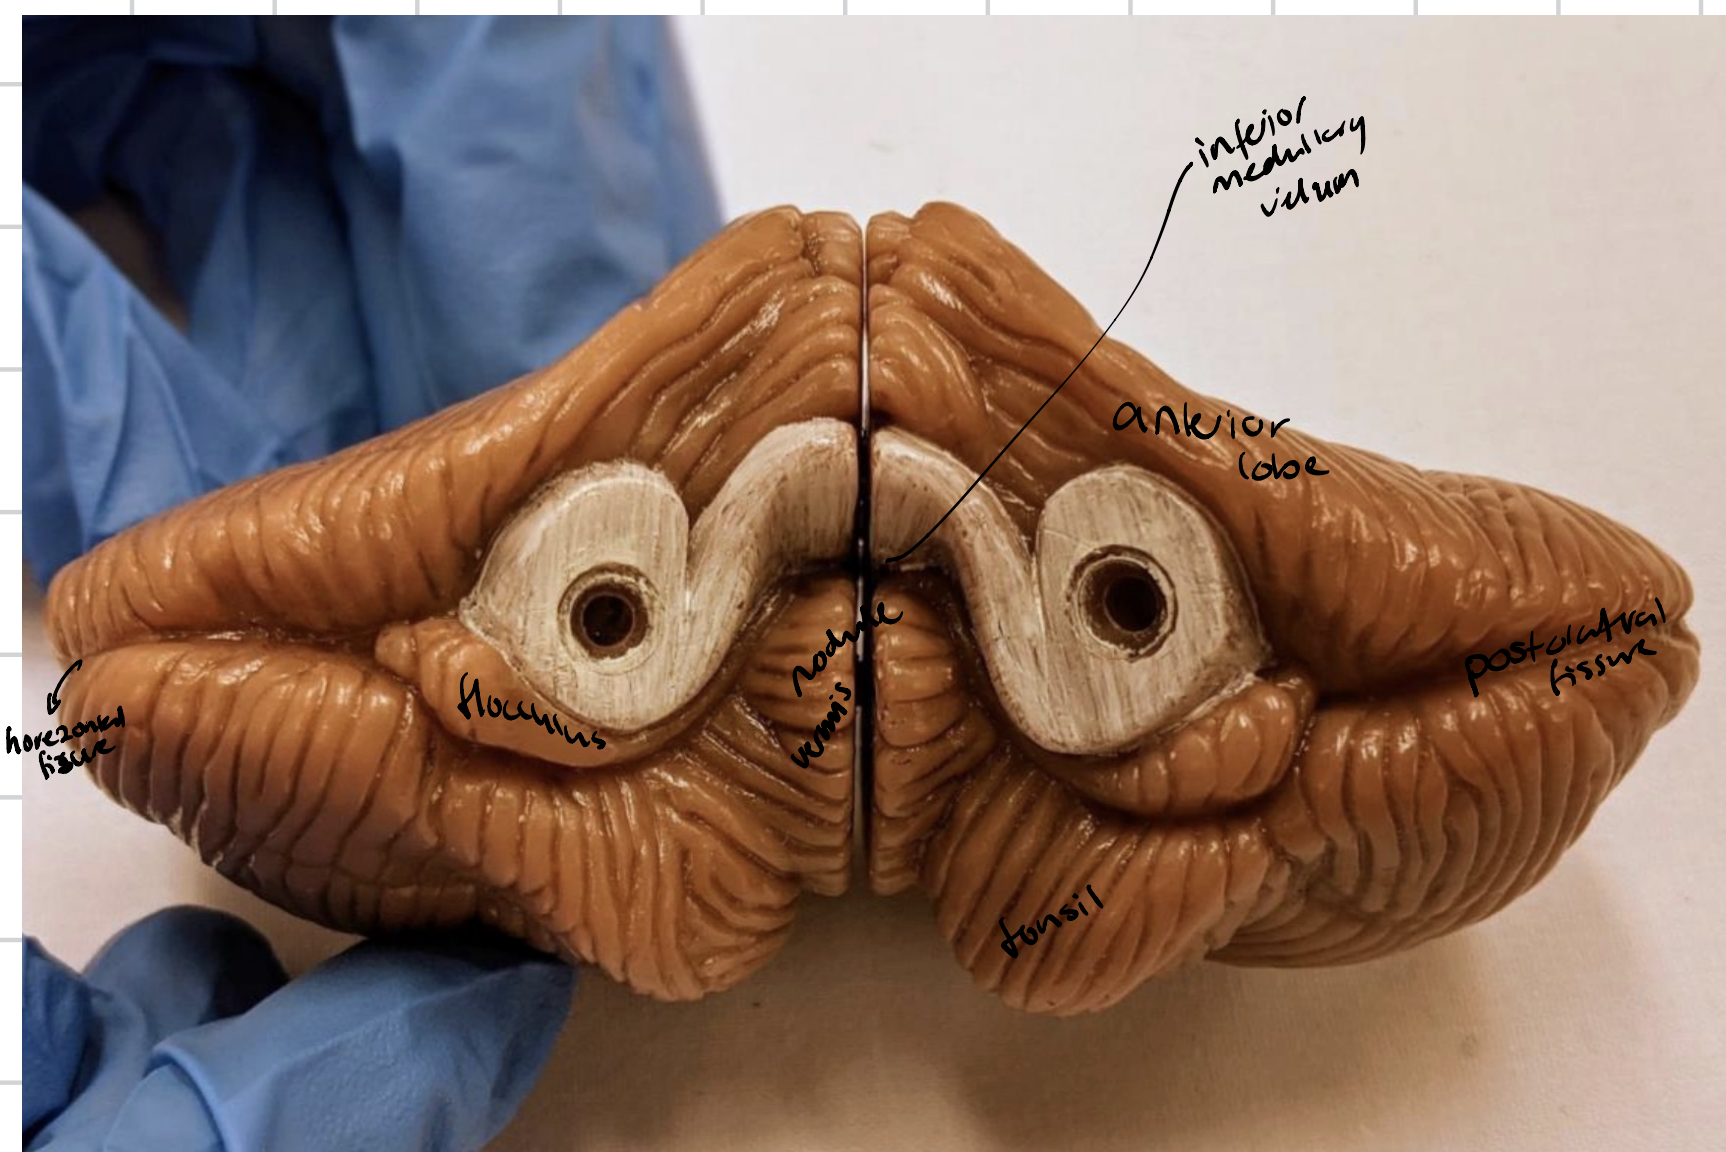

Cerebellum

Anterior lobe of cerebellum

Horizontal fissure

Posterior lobe of cerebellum

Cerebellar tonsils

Posterolateral fissure

Superior medullary velum

Arbor vitae

Folia